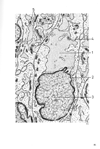

神経核;核【しんけいかく;かく】 Cluster of neurons outside of the cortex.(神経系ではある一つの機能にかかわる神経細胞の細胞体は集団を形成する傾向があり、この集団は末梢神経系では神経節、中枢神経系では神経核とよばれる。)